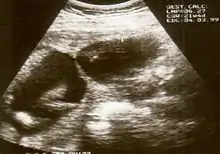

The diagnosis of constriction ring syndrome can be confirmed with an ultrasonography. The clinical manifestations can be extremely variable. It could be a single or multiple manifestation. This can be confirmed at the end of the first trimester or at the beginning of the second trimester.[13] But not every patient will be diagnosed at that moment, most will get this diagnosis at birth.

Individual strands are small and hard to see on ultrasound, so bands are detected indirectly because of the constrictions and swelling upon limbs or digits. Misdiagnosis is also common, so if there are any signs of amniotic bands, further detailed ultrasound tests should be done to assess the severity. 3D ultrasound and MRI can be used for more detailed and accurate diagnosis of bands and the resulting damage/danger to the fetus.